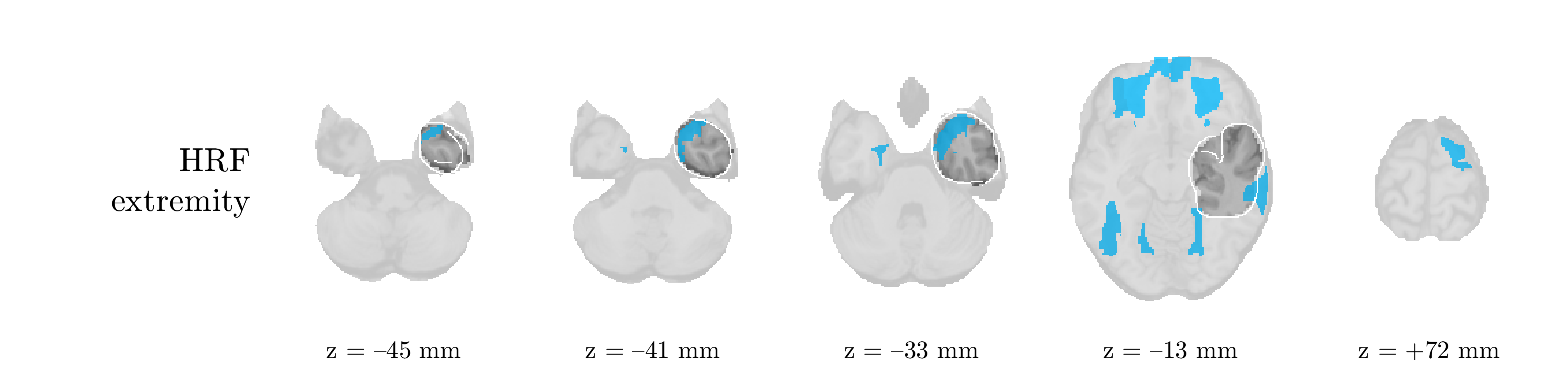

We analyze the solution with sources. Figure 1 shows the EEG signatures and HRF waveforms. One of the sources is highly correlated to the MWF reference (in grey), which was already known from Table B.3. This IED-related source had a typical low-frequency spectrum, which is expected for the typical spike-and-wave interictal discharges. The topography is relatively diffuse, although the highest amplitudes are mostly in the left hemisphere. This is in accordance with the lateralization of ictal onset zone (left temporal lobe, cfr. Table 1). There are some noteworthy observations to be made about some of the other components. The fourth has an unusually sharp spectrum, is mainly localized on two nonadjacent center electrodes, and is sustained for a single period of many seconds Hence, this component likely captured an artifact (of yet unknown origin), although we spotted no large-amplitude changes in the EEG itself. Similarly, the third source is only present at one frontal electrode, and exists in a frequency range above 20 Hz. It might represent a muscle artifact, e.g., due to frowning or twitching of some muscles in the forehead. The HRFs of all ROIs are shown in Figure 1(b). Two of the basis functions seem to have converged to a very similar waveform, which is an unfortunate possibility if two initial HRFs are too close to the same local optimum in their respective parameters. This reduces the expressive power of the basis set, which is clearly visible, since many ROIs have a nearly identical HRF. One of the twenty ROIs with the highest-entropy HRF overlapped the IOZ, although clearly this HRF (bold line) is not among the most dissimilar waveforms for this patient. This is also visible in Figure 2: both the HRF entropy and extremity maps show a small overlap with the delineated IOZ. Despite the good correspondence in the EEG domain, no significant (de)activation of the IED-component is found inside the IOZ.

We analyzed the solution with sources, and show the results in Figure 5 and 6. There is one source which is mostly correlated to the reference (but not extremely, see also Table B.3). This source had a right-temporal focus, conform the diagnosis in Table 1. The second source illustrates the phenomenon of an erroneous sign exchange between the spatial and spectral profiles. Also one of the HRFs has a negative polarity, which is a failure of the sign correction procedure (in this case, because there is exceptionally no positive overshoot). However, the HRF variability metrics are still interpretable, and indeed two ROIs among the ones with the highest-entropy HRFs overlap with the IOZ. The IED component is significantly active in a tiny portion of the IOZ (cfr. Figure 6). The second source is significantly active in symmetrical parts of the parietal lobe. Given its ongoing fluctuation over time, we hypothesize that this source captures a resting state network (RSN).

We analyze the solution with sources, and show the results in Figure 7 and 8. There is a clear IED-related component, with a very high correlation to the MWF reference, a typical spectrum, and an anterior-temporal focus, which corresponds very well to the patient’s diagnosis (cfr. Table 1). The fifth source seems present at only one channel, and has spectral harmonic at Hz and Hz. One of these peaks is reminiscent of the fourth component in patient 1. As Figure 8 shows, the HRF entropy and extremity prove to be strong biomarkers for the IOZ in this case, and also the significant IED activation and deactivation allow correct localization. In Figure 7, it is clear that some HRFs may still have the wrong sign, which means that the interpretation of ‘active’ and ‘deactivated’ is flipped in those ROIs. Hence, regions of significant deactivation are in fact significantly activated. The fourth source had a significant overlap with the auditory RSN, and its spectrum reveals activity in the band.

We analyze the solution with sources, and show the results in Figure 11 and 12. We found a clear IED-related component, with a characteristic spectrum and a topography which is backed up by the patient’s diagnosis (left anterior-temporal IOZ). The fourth source has a very similar topography and spectrum to the fifth source in patient 5. One HRF inside the IOZ had a high-entropy, and is distinguishable from the others by its very sluggish waveform, i.e., it is smeared out in time, with no sharp over- or undershoot. Also the pseudo t-map provided an accurate localization of the IOZ. Notably, in this patient, the extremity metric misses the deviating HRF in the IOZ (while the entropy metric picks it up). The second source overlapped with the frontal part of the default mode network (DMN), and is active in the and low bands.

We analyze the solution with sources, and show the results in Figure 15 and 16. In this patient, there is only a moderate correlation of a component with the MWF reference time course. This component’s topography (left occipital) agrees with the clinical description, however. The HRF extremity (and not the entropy) is high in a small part of the IOZ. Both the significant IED activation and deactivation allow correct localization as well. The second source seemingly captured high-frequency oscillatory activity in the sensorimotor network, similar to the previous patient.

We analyze the solution with sources, and show the results in Figure 17 and 18. The IED-related source had a high correlation with the MWF reference, but an odd bimodal spectrum. Its EEG topography is very consistent with the clinical description. Both HRF extremity and entropy are useful biomarkers for the IOZ. The IED activation and deactivation maps each had a very small overlap with the IOZ. The second source is temporally sparse and captures high-frequency EEG variations, which we identified as muscle artifacts.

We analyze the solution with sources, and show the results in Figure 19 and 20. Again we observe an IED-related source and a seemingly artifactual source with a spectral peak near 34 Hz. Many of the high-entropy HRFs are highly noncausal, and are associated to ROIs inside the IOZ. Hence, with both HRF metrics, the highest-scoring ROIs provides good localization of the HRF. While there are no significantly active ROIs in the IOZ, there are several significantly deactivated ROIs, which may indicate that the sign standardization was not done flawlessly (cfr. also some of the negative-peaking HRFs for patient 10). Surprisingly, the second source had one significantly active ROI, which overlaps with the IOZ, but which did not match its EEG topography. Hence, the nature of this source remains ambiguous.